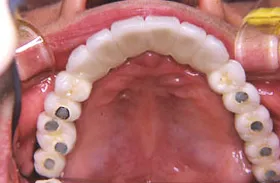

重度の歯槽膿漏のケース

■治療前

■治療後

上下に入れ歯を入れていましたが、ここ数年しっかりと噛む事がなかった患者様です。何でもおいしく食事ができるようになりたいと希望され、来院されました。

治療法としては、最小限のインプラントの本数で対応ができるように、オールオンフォーを意識した治療法で対応させて頂きました。

| 主訴 | 噛めない |

| 治療方法 | 上顎8本、下顎6本のインプラントを埋入し固定性の入れ歯で治療した |

| 治療期間 | 約1年 |

| 通院回数等 | 20回 |

| 費用 | 上顎4,130,000円 下顎3,630,000円(税込) |

| リスク・副作用 | 治療後に一時的に腫れることがある |